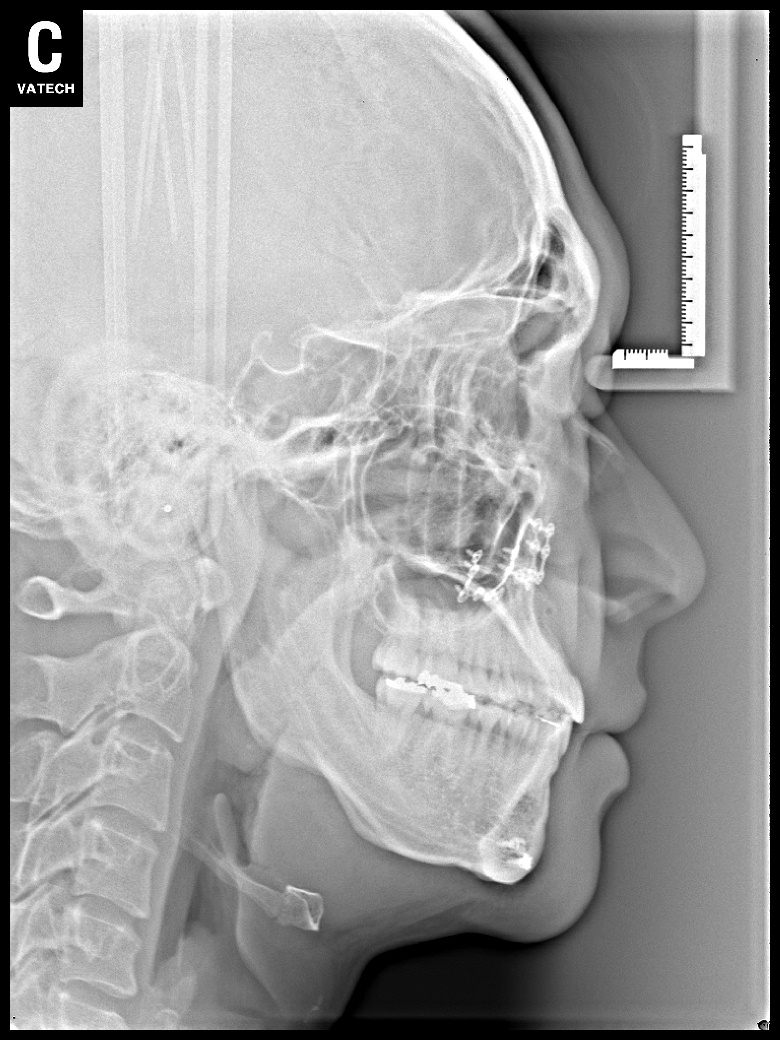

치료 후 사진입니다.